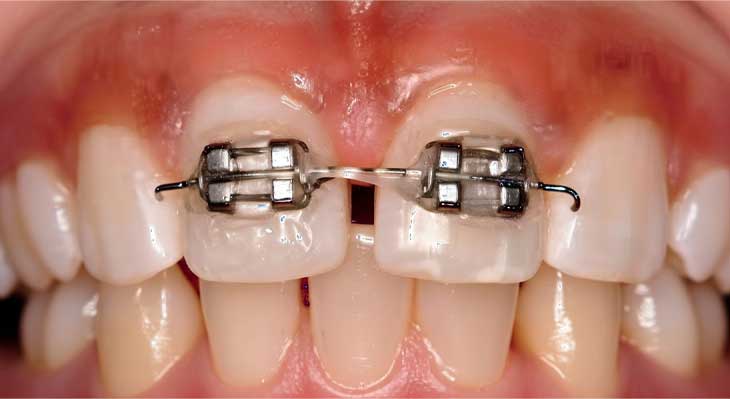

- بریس های فلزی (درمان سگمنتال): در این روش، بریس های فلزی تنها بر روی بخش جلویی دندان ها نصب می شوند که هزینه کمتری دارد.

- ارتودنسی ثابت ۶ ماهه: این یک رویکرد درمانی سریع است که با تمرکز بر روی دندان های جلو، مشکلات زیبایی را در مدت کوتاهی حل می کند.